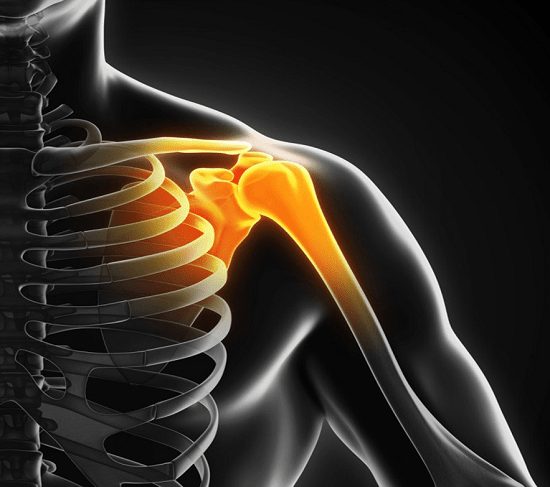

لابروم نوعی غضروف در مفصل شانه است. شانه یک مفصل توپ وحفرهای درمحل اتصال بازو به بدن میباشد. استخوان بازو (هومروس) در شانه یک توپ متصل به حفره را شکل میدهد که بخشی از استخوان تیغهای شانه است. این دو استخوان توسط رباطها به یکدیگر متصل میشوند – بافتهای محکمی همانند بند که استخوانها را در ارتباط با یکدیگر نگه میدارند. ترومای حاد یا حرکات تکراری مفصل شانه یکی از علل اصلی مشکل اسلپ )صدای ترق تروق) در بین ورزشکاران است. اما خوشبختانه پزشکان میتوانند با کمک فیزیوتراپی به این بیماران کمک کنند.